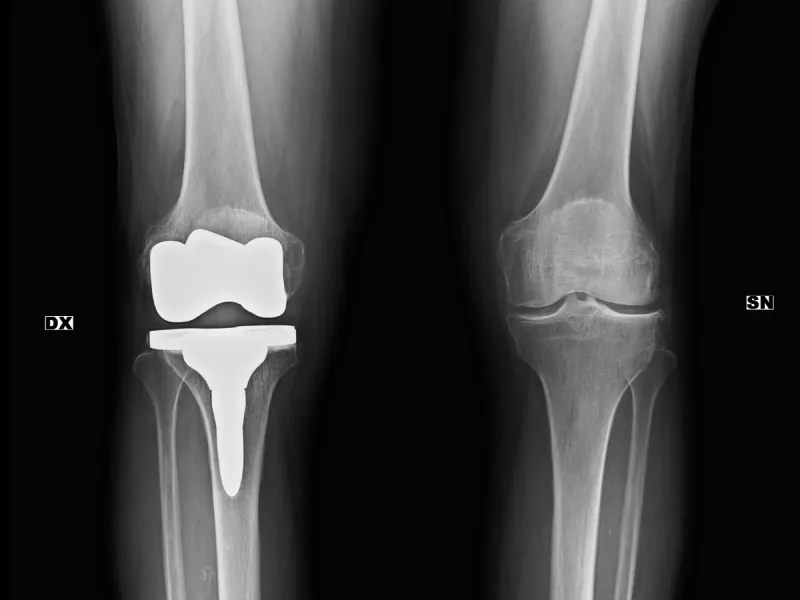

1. Empezá por la base: la radiografía (Rx)

La radiografía suele ser el primer contacto del médico no especialista con la imagen. En el post vas a ver lo esencial: cómo se forma la imagen, qué degrada la calidad y por qué aparecen errores típicos.